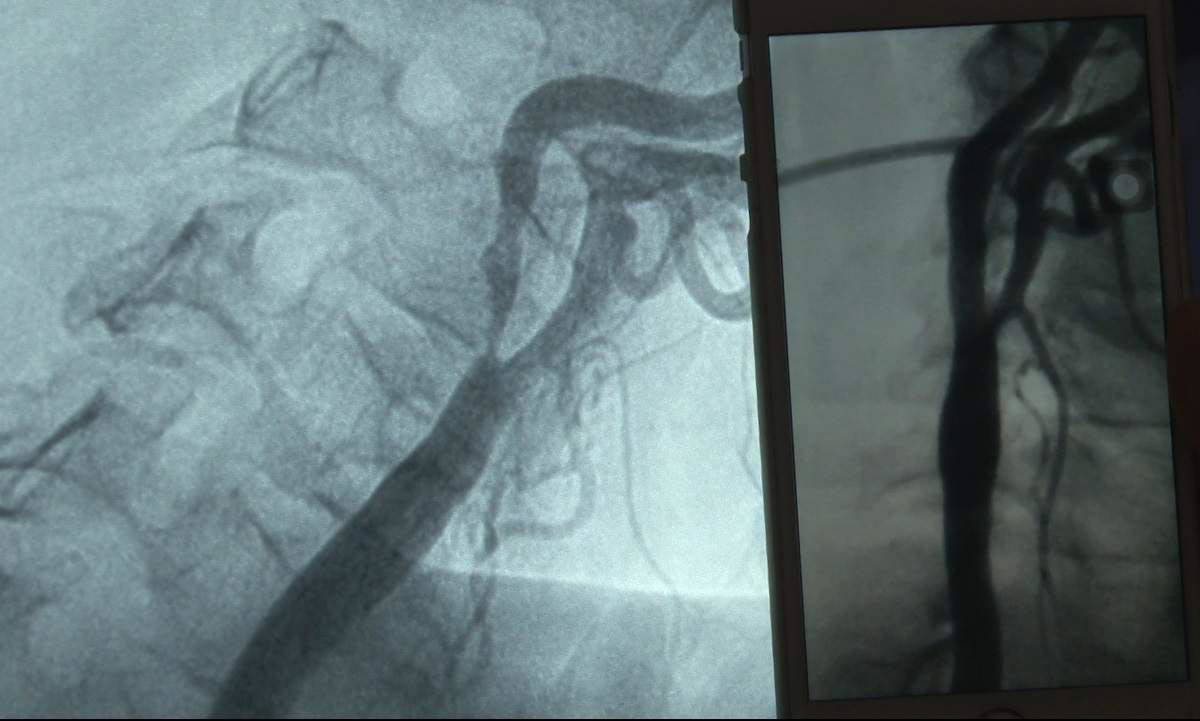

Şimşek, "Kol, akciğer ve kalp damarında pıhtı olan hastalarla karşılaştık. Koronavirüs hastalığının vücutta pıhtılaşmaya meyil oluşturduğunu artık biliyoruz. Dolayısıyla geçirmiş hastalarımızın kalp ve damar hastalıkları açısından semptom dediğimiz yani belirtileri oluşursa ihmal etmeden kalp damar uzmanlarına görünmesinde fayda var. Kalp damarlarıyla ilgili olduğu vakit göğüste sıkışma, yanma ve kalp krizi ile kalp spazmının belirtileri oluyor. Vücudun başka bir yerinde benim karşılaştığım hasta gibi kol damarında pıhtı oluştuğu zaman akımı etkileyense kolda uyuşma, soğukluk ve nabız kaybı olabilir. Kocaman bir pıhtı çıkardık hastamızın birinde. Akciğer damarlarında pıhtı oluştuğu vakit veya vücudun toplar damarlarında oluştuğu vakit akciğere attığında ciddi nefes darlığı oksijen santrasyonunda düşüklük ve nefes açlığı hissedebilir" diye konuştu.

Prof. Dr. Şimşek, hastaların bu durumu dikkate almaları gerektiğini hatırlatarak, "Bu ve buna benzer kalp ile damar hastalığının düşündüren semptomları olan hastalar özellikle koronavirüsten sonraki ilk 1 ay veya 20 gün içinde bu ve benzeri semptomlarla karşılaştıkları vakit geçirmeden kalp ve damar hastalıkları uzmanına başvurmalarında fayda var çünkü zaman geçtikçe o bölgede oluşan pıhtı ilaç tedavisine cevap verme yanıtları azalıyor ve kronikleşiyor. Dolayısıyla akciğerde oluştuğu zaman kronikleştiği için kronik bir akciğer tansiyonu oluşuyor ya da kolda oluştuğu vakit daha sonra bunu ilaçsız balon veya stent ameliyat çok daha zor komplike işlemlerle müdahale etmek zorunda kalabiliyoruz. Erken fark edildiğinde biz biliyoruz ki bu hastalar ilaç tedavisine yanıt verebiliyorlar. İlaçla biz bu pıhtıları çözebiliyoruz, kısmen büyük ölçüde" dedi.